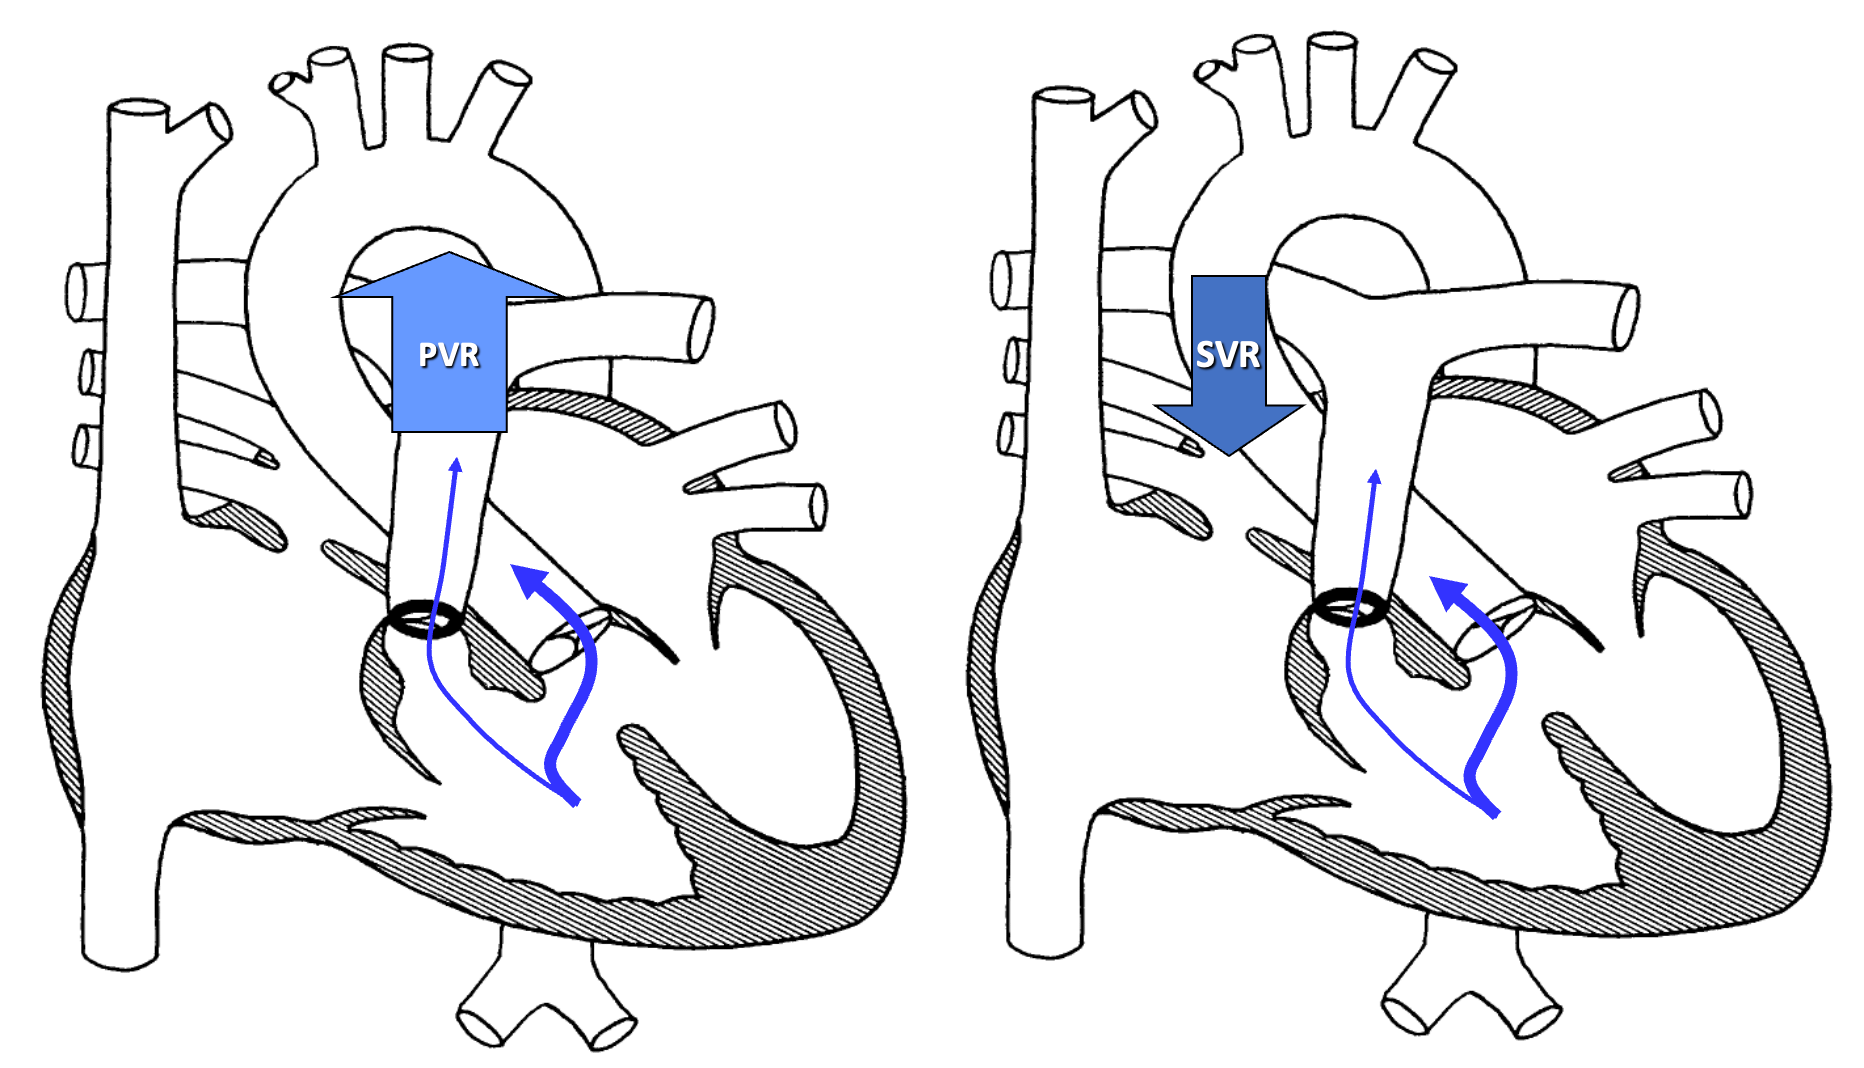

Knee-chest or squatting position increases afterload thus increasing systemic resistance

Phenylephrine increases afterload by promoting systemic vasoconstriction

Squatting

- Common with unrepaired TOF

- Increases oxygen saturations

- Angulation and kinking of femoral arteries with increased SVR, decreasing the R→L shunt

Tachycardia

- Impaired RV filling

- Increased RVOT obstruction

- Increased Rt→Lt shunt

- Increased Agitation

- Hypovolemia

- Increased Age

- Increased PVR

- Hypercyanotic Spells (TET spells)

Increase systemic vascular resistance

- Squat/Knee chest position

- Ketamine 1-2mg/kg IV

- Neosynephrine 0.02mg/kg IV